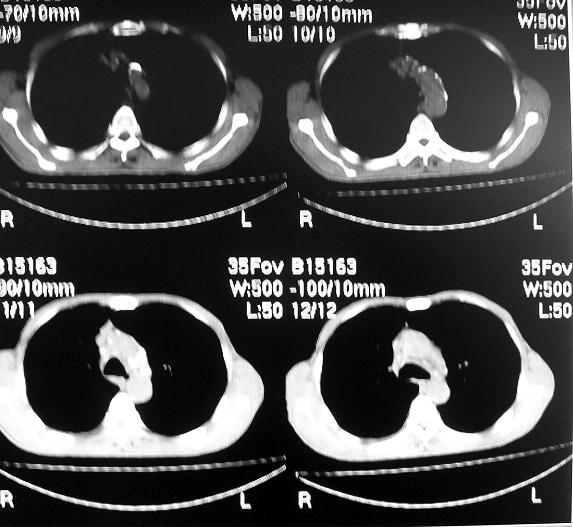

男63岁胸痛来诊

右下肺周围性肺ca并双肺及右侧胸膜转移。[emb6]

左下肺ca伴双肺及纵隔淋巴转移

打错了,是右下肺

打错了,是右下肺ca

右肺病灶前缘不平整,略呈分叶状,其后方胸膜下脂线消失且似有向胸壁浸犯,左下肺球形灶内可见不规则空洞影,余双肺内可见多枚结节影,结合病史支持考虑肺癌肺内转移胸膜转移,便双肺后部病灶倒也是结核好发区域,建议穿刺活检

右下肺周围性肺ca并双肺及右侧胸膜转移。支持

右下肺周围性肺ca并双肺及右侧胸膜转移。

右下肺周围性肺ca并双肺及右侧胸膜转移。单看病变像炎性假瘤。

右下肺癌,双肺及胸膜转移

右下肺癌伴双肺及胸膜转移。